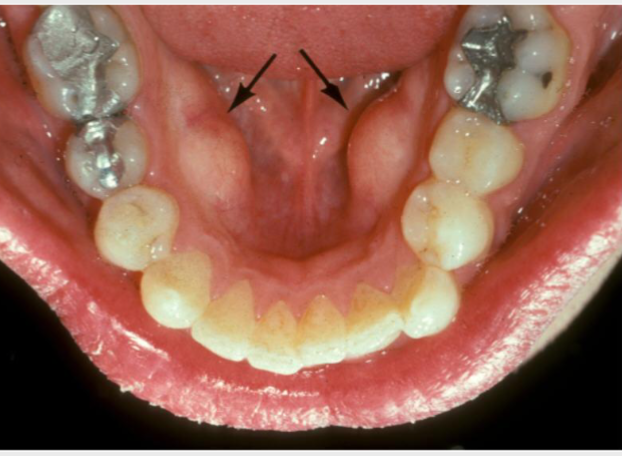

mesiodens

a type of supernumerary tooth that typically occurs between the MAX CENTRAL incisors